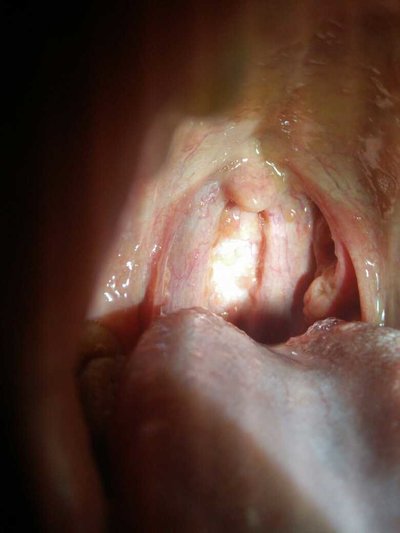

In recent days, I am always a little irritable. There are many things in my family. I have just had a baby. I can't go out when I'm in confinement and feeding. I'm almost depressed. But we can't just go out on our own regardless of the children. Sometimes regret not, really should not get married, married everything changed, but it is not what I want. Recently, I don't know if I'm on fire. My tongue coating is gone. My tongue is red. I don't want to eat. I can't eat it. I don't know what can make me better. So what's the reason for a big piece of tongue coating? Let's talk about it

Under normal circumstances, consider the symptoms of fire, may also be glossitis, no tongue coating is a very serious situation, do not ignore, it is recommended that timely medical treatment. May also be the cause of inflammation of the tongue, is not the usual diet do not pay attention to health, oral bacterial infection is possible.

Tinea lingualis is also possible, but usually we should pay attention to the lack of trace elements or vitamins in the body. So usually we must pay attention to eat more protein, vitamin rich food, we must pay attention to reasonable diet. Eat spicy food.

No tongue coating, red tongue, may also be the cause of spleen and stomach deficiency cold, this will lead to a decline in diet, do not love to eat, sleep naturally will not be good, the spirit of the good look will not be good, so usually we must pay attention to eating habits. We should pay attention to the symptoms of spleen and stomach deficiency cold.